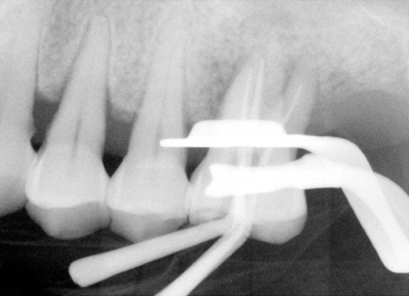

| 图七 牙周手术中:结石(箭头) | 图八 根尖切除前根尖片 |

2010-1-22 病人回诊所仍觉得疼痛没有改善,冷热痛,夜间痛,要求拔牙,检查表明:左上6号牙有轻度扣痛,颊侧根分叉处,以及鄂侧根鄂面有探痛,分析术前X光片(图八),好像远中根牙胶尖充填不到位,可能是术后疼痛原因,残余牙髓炎,所以我们准备作根尖切除术。翻瓣,根尖骨板完整,用高速牙钻开窗,一时找不到远中根尖,再拍一张根尖片(图九),适当调整后,我们找到了远中根尖,并作了切除术(图十),然后根尖倒充(IRM,图十一),生理盐水冲洗,缝合伤口。